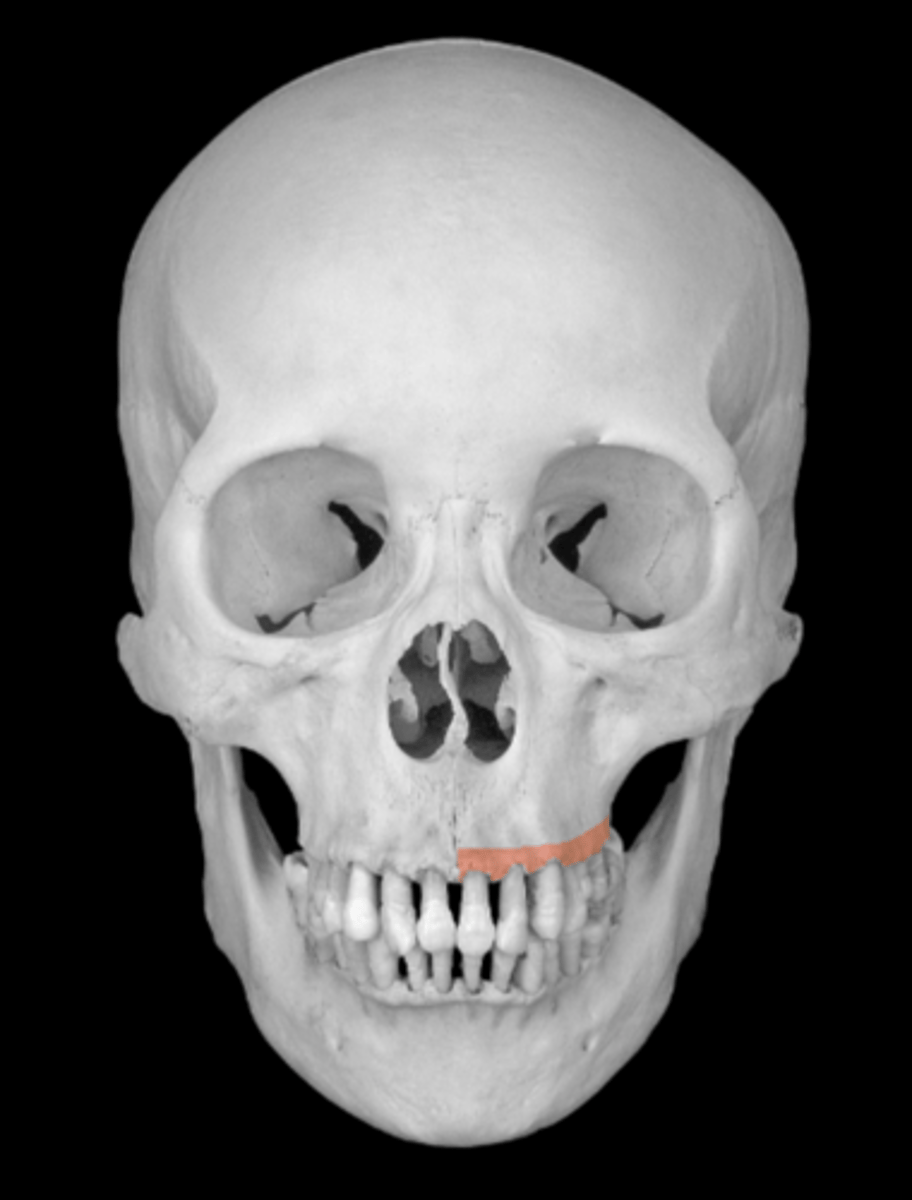

intermaxillary suture of maxillae

alveolar process of maxillae

dental alveoli of the maxilla